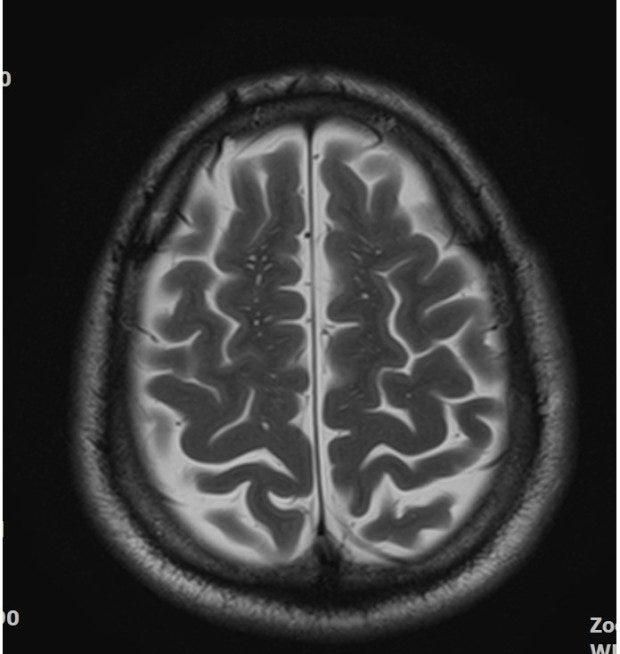

• 3번 째 사진

뇌MRI를 촬영했는데 뇌실질에 자그만한 하얀점이 많이 있어서 걱정이 되셨군요

말씀하신 뇌실질에 하얀 병변은 소혈관질환이라고 합니다.

약간 과격한 표현을 쓴다면 작은 뇌경색이라고 보시면 될 것 같습니다.

그러니까 동맥경화의 결과로 인하여 작은 혈관에 문제가 생긴 것이지요

• 올려주신 영상은 뇌 T2 강조 영상의 정상적인 대뇌겉질(gyri) 주름 구조가 보이는 형태에 가깝습니다. 질문하신 “좁쌀 같은 하얀 점”은 영상상 뇌겉질의 주름 사이로 보이는 정상 신호거나, 정상 혈관 단면·미세 구조로 보일 가능성이 높습니다.

1. 미세 허혈(약한 혈관성 변화, 작은 백질변성)

– 고혈압·당뇨가 있는 경우 40대 후반~50대부터 서서히 나타날 수 있음

– 아주 초기 단계에서는 작은 점 형태로 보이기도 함

– 대부분 경미한 경우 임상적으로 큰 문제는 없지만, 장기적으로는 관리가 필요함

현재 사진 한 장만으로 ‘병변’이라고 단정하기는 어렵습니다.

실제 판독에서는 같은 부위를 다른 시퀀스(T1, FLAIR 등)에서 비교해 미세허혈인지 정상 구조인지 판단합니다.

정식 판독문 확인 + 신경과 상담을 권합니다. 특히 판독에서 “소혈관병(small vessel disease)”, “white matter hyperintensity”, “미세허혈” 등이 언급되는지 확인하는 것이 좋습니다.